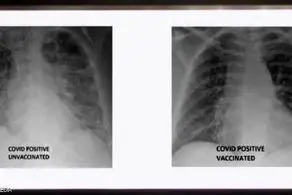

به گزارش منیبان، علی اسدااللهی امین فوق تخصص عفونی، در برنامه «طبیب» با اشاره به اینکه اگر با همین منوال و بدون قرنطینه و محدودیت ادامه دهیم تعداد ابتلا و فوتی‌ها چندین برابر خواهد شد، عنوان کرد: امیدواریم در جلسه جدید ستاد ملی کرونا تصمیمات عاجلی گرفته شود، چون این وضعیت فعلا با واکسیناسیون هم کنترل نمی‌شود، چراکه تازه بعد از دو هفته از دوز دوم است که واکسن عمل می‌کند و اثرات اجتماعی آن دو تا سه ماه بعد مشخص می‌شود.

این پزشک متخصص همچنین در خصوص صحبت‌هایی که در خصوص عوارض برخی واکسن‌ها از جمله آسترازنکا برای سنین زیر 50 سال  شده، اظهار کرد: هر واکسن یک سری مزایا و یک سری عوارض دارد که متخصصان باید در این خصوص مرتبا به حاکمیت مشورت دهند و راه را اصلاح کنند، البته در کشورهای دیگر که واکسن‌های دیگر به وفور هست توصیه‌هایی می‌شود که بهتر است مثلا فلان واکسن به فلان گره سنی تزریق نشود.

اسداللهی در ادامه تأکید کرد: اما سازمان جهانی بهداشت آن را منع نکرده و تزریق آن هم برای افراد زیر 50 سال در شرایطی که واکسن دیگری در دسترس نبود منعی ندارد، اما اگر واکسن دیگری وجود داشت از واکسن‌های دیگر استفاده شود، بنابراین نباید مردم را بترسانیم. زنان باردار هم می‌توانند واکسن تزریق کنند و برای آنها بیشتر سینوفارم پیشنهاد می‌شود، همچنین بهتر است که دوز دوم هم از نوع دوز اول باشد اما اگر نبود می‌توانند از واکسنی که پیشنهاد می‌شود استفاده کنند، البته در برخی مطالعات نیز نشان داده که این امر تأثیر بیشتری هم داشته است.

وی در پایان نیز یادآور شد: خوردن لبنیات، استفاده از ویتامین‌ها از جمله بیوتین و همچنین مسکّن بعد از زدن واکسن هم هیچ منعی ندارد، اما قبل از زدن واکسن مسکّن خاصی استفاده نکنید چون ممکن است از اثرگذاری واکسن کم کند، همچنین فردی که واکسن زده نیاز به قرنطینه ندارد چون ناقل نیست مگر اینکه به واسطه تماس با فرد بیمار ناقل ویروس باشد.